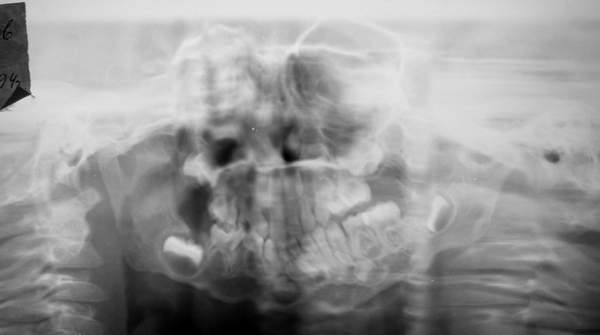

Пациент В., 13 лет. Диагноз: Костный анкилоз левого височно-нижнечелюстного сустава (ВНЧС), левосторонняя микрогения. Болеет с 2-х летнего возраста. Возможная причина развития анкилоза – воспалительный процесс (в первые 1,5 года жизни часто болел простудными заболеваниями, травму родители отрицают). В 3 и 5 лет проводилась редрессация – безуспешно.Прилагаются: ортопантомограмма, кадры СКТ с 3Д реконструкцией. Вопросы: определение тактики лечения – вид и сроки реконструктивно-пластической операции (этапов операции), а именно – неоартропластики и устранения микрогении, медикаментозная терапия в до- и послеоперационный период, ортодонтическое лечение.